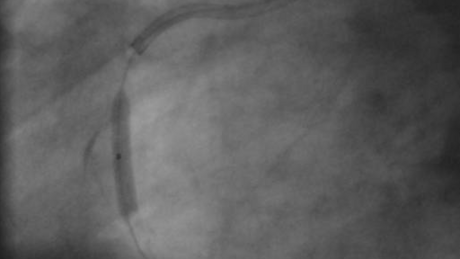

Bild 1: Verschlossene rechte Herzkranzarterie wie bei einem Herzinfarkt